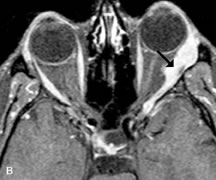

INTRAOCULAR TUMORS

On MRI, uveal melanomas have a typical appearance that helps to differentiate them from other primary and secondary intraocular tumors as well as choroidal detachments. Pigmented melanomas are hyperintense on Tl-weighted images, hypointense on T2-weighted studies, and hyperintense on proton density–weighted examinations (Fig. 24).30,31,50,80–82 These signal characteristics have been attributed to the paramagnetic properties of melanin because of stable free radicals that shorten the T1 and T2 relaxation times. Moderate enhancement is seen on postgadolinium T2-weighted images. Gadolinium-enhanced T1-weighted images are particularly sensitive in detecting choroidal melanomas.83 MRI may be less sensitive in detecting extrascleral extension of tumor than echography performed by an experienced ultrasonographer.84

Fig. 24. A. T1- and (B) T2-weighted MR scans demonstrate a small nodular intraocular mass (arrows) that is very hyperintense on the T1-weighted scan and hypointense on the T2-weighted image. This signal intensity pattern is due to the presence of free radicals within melanin granules. C and D. Postcontrast fat-suppressed T1-weighted scans demonstrate homogeneous intense enhancement of the lesion and no evidence of seleral penetration or optic nerve invasion.